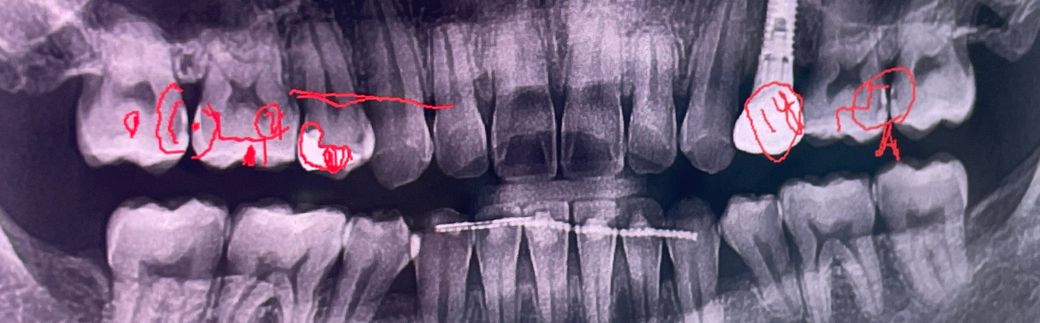

충치 진단받고 한곳에서는 인레이치료받아라하고 걱정되서 다른치과갔더니 좀더지켜보자하네요ㅜ 어찌할지모르겠는데 알려주시면감사하겠습니다

• 1번 째 사진

기존에 치료를 햇던 부분 아래부분에 충치가 다시 생긴거 같고 치아 사이에도 충치가 잇는것같습니다. 치료가 필요해 보입니다.

x-ray에서 치아와 치아 사이 즉 인접면에 충치가 보입니다. 충치가 보이니 치료해야 합니다.

엑스레이상 충치가 없는것은 아닙니다 다만 그걸 지켜보느냐 바로 치료하느냐는 치과의사마다 판단이 다를 수 있습니다